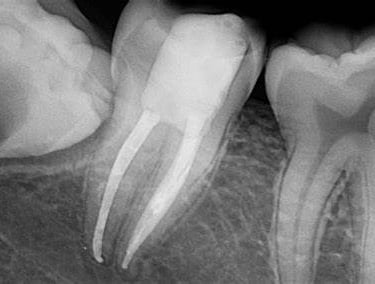

Our teeth, just like any other part of our body is also supplied by nerves and blood vessels. Its called the PULP of the tooth. And just like any other part of the body, it carries a risk of being diseased or infected.

Superficial infections or caries as we dentists call it still have a bright chance of being treated by normal tooth fillings. But many times patients report to us with lots of pain and strong sensitivity in teeth.

That is simply because the infection had reached the Pulp of the tooth and we have ignored the tooth for a long time.